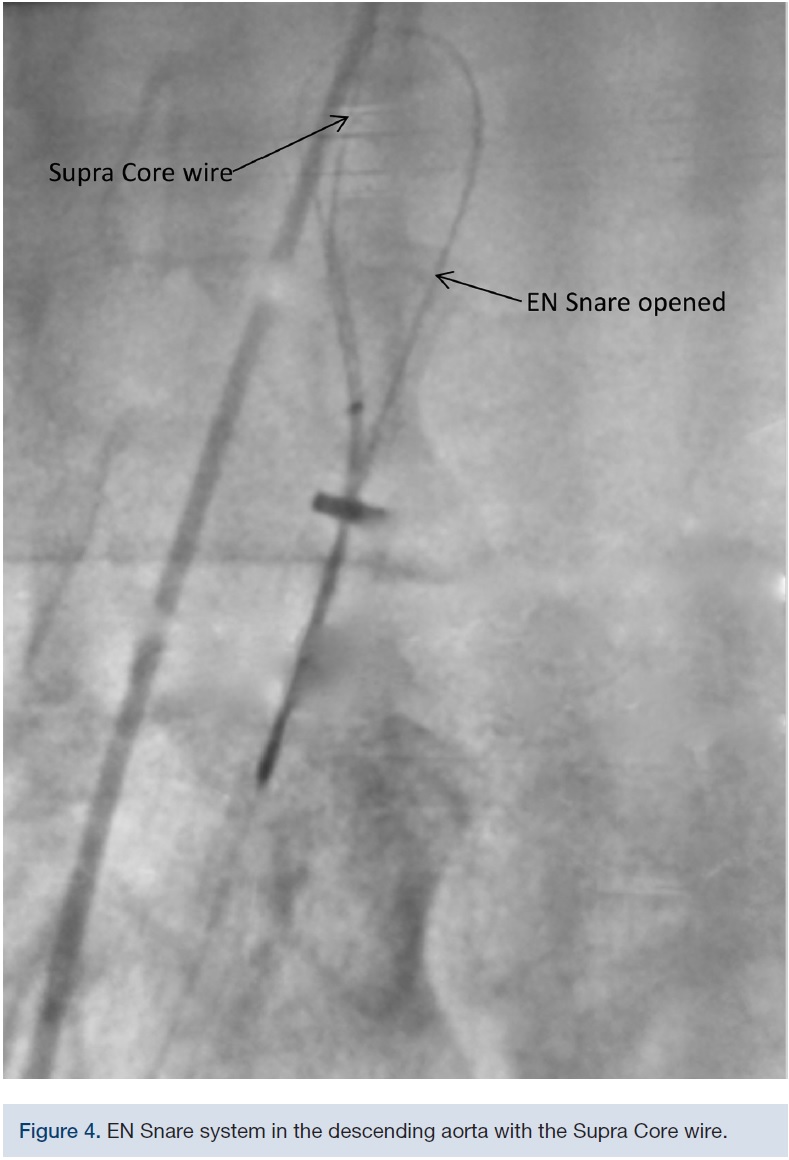

The 18F DrySeal sheath was placed through the right common femoral artery over an .035-inch Lunderquist extra stiff wire. A 4F micropuncture needle was advanced through the apical window into the left ventricular cavity. A micropuncture wire was advanced antegrade across the aortic valve into the ascending aorta. Finally, the micropuncture sheath was advanced over the wire into the ascending aorta, and the micropuncture needle and wire were removed. An .035 inch x 300 cm Supra Core 35 wire (Abbott Vascular) was advanced via the transapical sheath into the ascending aorta and ultimately, to the descending aorta. The transapical sheath was then removed. A triple-lobed EN Snare Endovascular Snare System (Merit Medical Systems) was inserted into the 18F femoral arterial sheath and the Supra Core .035-inch wire was trapped. Subsequently, a 6F pigtail catheter was advanced over the snared Supra Core .035-inch wire and placed into the left ventricle. The Supra Core .035-inch was replaced by a 260 cm Amplatz .035-inch Super Stiff wire (Boston Scientific) and advanced into the left ventricle through the pigtail catheter. The pigtail catheter was removed and an 18 mm Z-Med II balloon (B. Braun Interventional Systems) was inserted over the Amplatz super stiff wire. A standard balloon aortic valvuloplasty was performed in preparation of the valve positioning. After the balloon valvuloplasty, a 23mm CoreValve Evolut R was successfully deployed. A 22 mm True Dilatation balloon (Bard Peripheral Vascular) was utilized to perform post dilation aortic balloon valvuloplasty. The final result was a mild aortic insufficiency with a 5 mm transvalvular gradient.